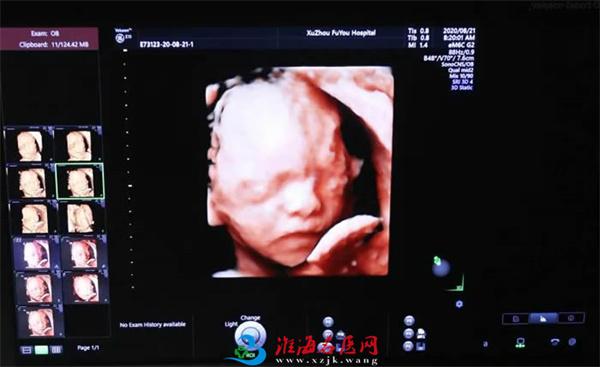

张丽主任介绍,无论是三维还是四维,都是在二维超声的基础上,利用计算机再处理技术达到立体模式重建的超声诊断技术,能看到胎儿的立体图形。“也就是说,三维彩超好比照相机,能捕捉胎儿立体静态的画面,四维彩超就像摄像机,可以看到实时动态的胎儿画面,比如:打呵欠、手舞足蹈的过程。”

也就是准妈妈常说的四维彩超,是对胎儿全身大结构的系统筛查